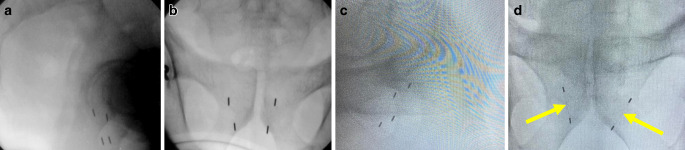

Methods: A retrospective analysis of 64 patients receiving transrectal ultrasound (TRUS)-guided transperineal implantation of ≥ 3 prostate FM and robotic SBRT between January 2011 and May 2021 was performed. Adverse events (AE) were classified according to the Society of Interventional Radiology (SIR) classification system. Digitally reconstructed radiographs (DRR) and the planning CT constituted the basis for implant geometry calculations. Marker detection rates were obtained from the Synchrony® (Accuray®) log.

Results: Complication rates were low, with mostly mild AE. Double FM significantly improved the rate of obtaining an optimal implantation geometry. High FM detection rates during treatment could be achieved independent of implantation geometry and type of FM. BMI and prostatic gland volume did not correlate with geometry and detection quality. An implantation-to-treatment interval of > 42 days was predictive for lower detection rates.